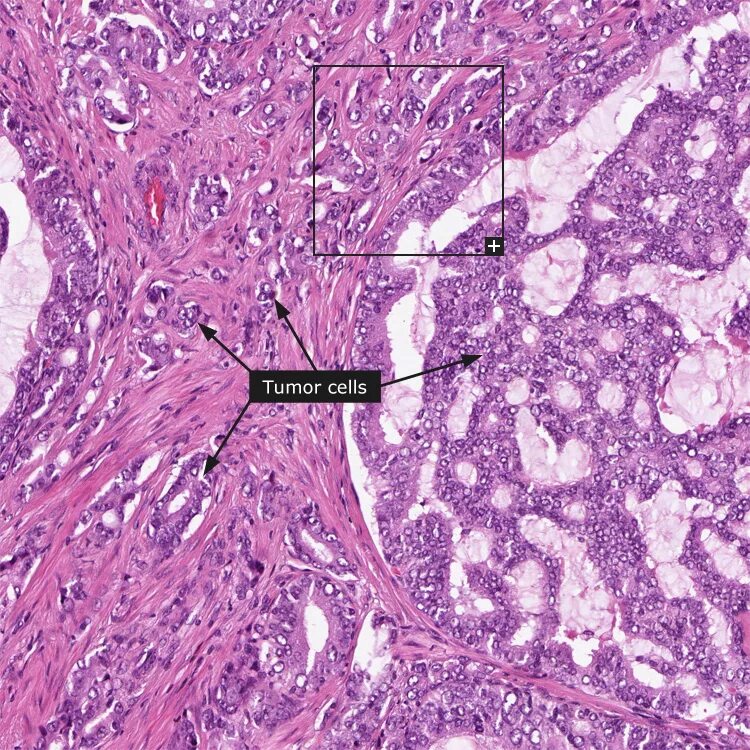

Гистология аденокарциномы